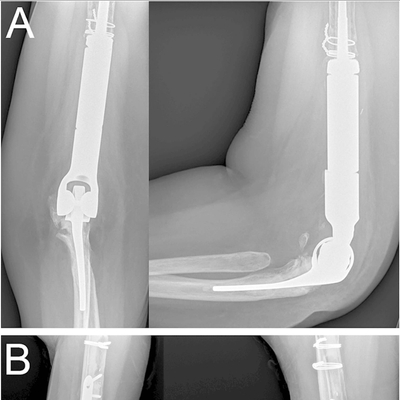

Click on an image below to view more info.